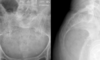

3

Q

What is the orientation of the fracture and the causative mechanism?

A

Transverse fracture due to tension/shear force

May be pathological